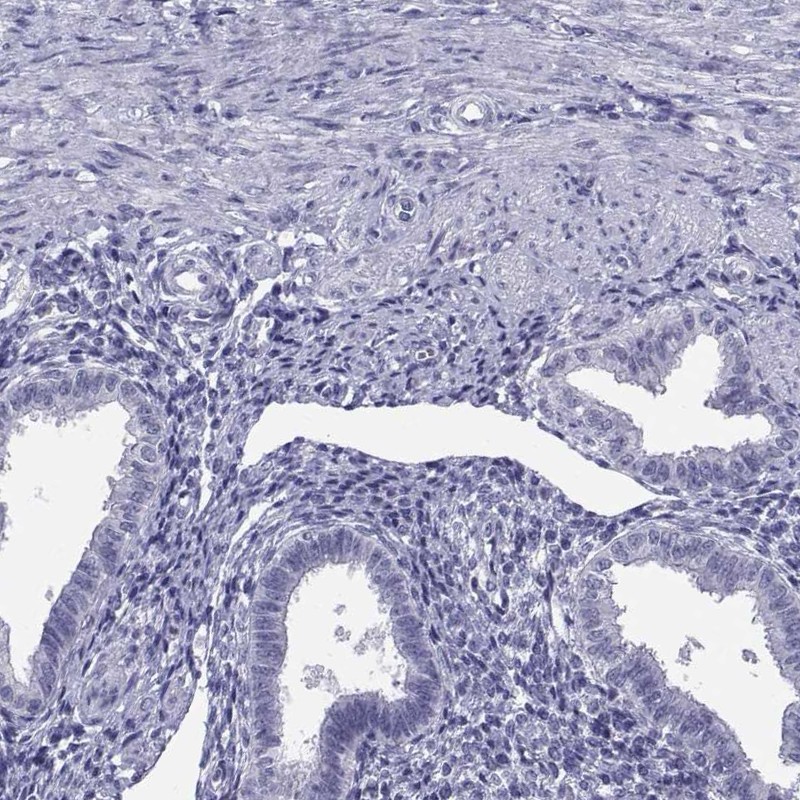

Immunohistochemistry analysis in human testis and endometrium tissues using Anti-TEX13A antibody. Corresponding TEX13A RNA-seq data are presented for the same tissues.